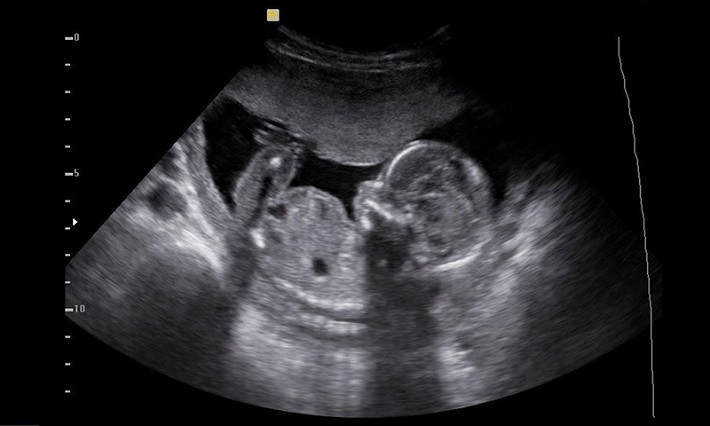

آزمون سونوگرافی با استفاده از امواج صوتی تصاویری از جنین و رحم ارائه میدهد. این تصاویر به پزشک کمک میکنند تا اندازه جنین، موقعیت جنین، وجود هر گونه عیب خلقی یا نقص ژنتیکی را ارزیابی کند. آزمایش خون نیز با اندازهگیری سطح هورمونهای خاص در خون مادر، ممکن است نشان دهد آیا جنین با خطر ابتلا به بیماریهای خاصی روبرو است یا خیر.

سونوگرافی دوم به پزشک این امکان را میدهد که جزئیات دقیقتری از اندازه و ساختمان اعضای جنین را بررسی کند. در صورت شناسایی هر گونه نقص ژنتیکی، تصمیمگیری در مورد ادامه یا قطع بارداری ممکن است صورت گیرد.

تعیین جنسیت جنین تابا یکی از مسائل مورد توجه در حین بارداری است. امروزه، با پیشرفت فناوری، تکنیکهای مختلفی برای تعیین جنسیت جنین وجود دارد. یکی از روشهای معمول، آزمون سونوگرافی است که به وسیله آن میتوان جنسیت جنین را با دقت تعیین کرد. این آزمون معمولاً در هفتههای ۱۸ تا ۲۲ انجام میشود و به والدین این امکان را میدهد تا جنسیت آینده نوزاد خود را بدانند.